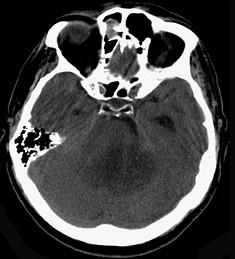

问题 听神经瘤(如图所示)的最常见症状为()

选项 A.头痛、呕吐 B.面部麻木,痛觉减退 C.眩晕,单侧耳鸣,耳聋 D.吞咽困难,进食呛咳 E.小脑运动共济失调

答案 C